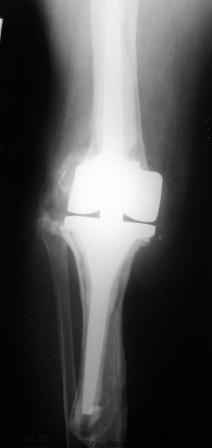

Нестабильность эндопротеза коленного сустава

Уважаемые коллеги! Хотелось бы услышать Ваше мнение о возможности и способе помощи больной. 1939 г.р. В 1995г. эндопротезирование правого коленного сустава протезом Феникс, в 1999г. в г. Томске - ревизия - ротационный хинч W.Link.

C 2005г. прогрессирует варусная деформация за счет нестабильности тибиального компонента. Попытка ортезирования - без эффекта. Попытка направить в ФСМУ без эффекта, да и больная не хочет никуда ехать. С уважением, Leonid